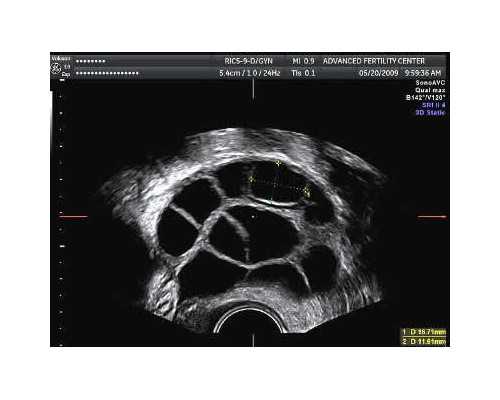

孕妇的血液标本被抽出后,首先经过两次高速离心处理,将上层的清液移入新的无菌管内,冷冻保存备用。然后应用试剂将上清液中的DNA提取出来,将其染色,放在在紫外灯下观察。

如果看到SRY的条带意味着是男孩,没有则表明是女孩,而且伴随胎儿不断长大,DNA浓度还会越来越高,并在受孕后8周达到高峰。